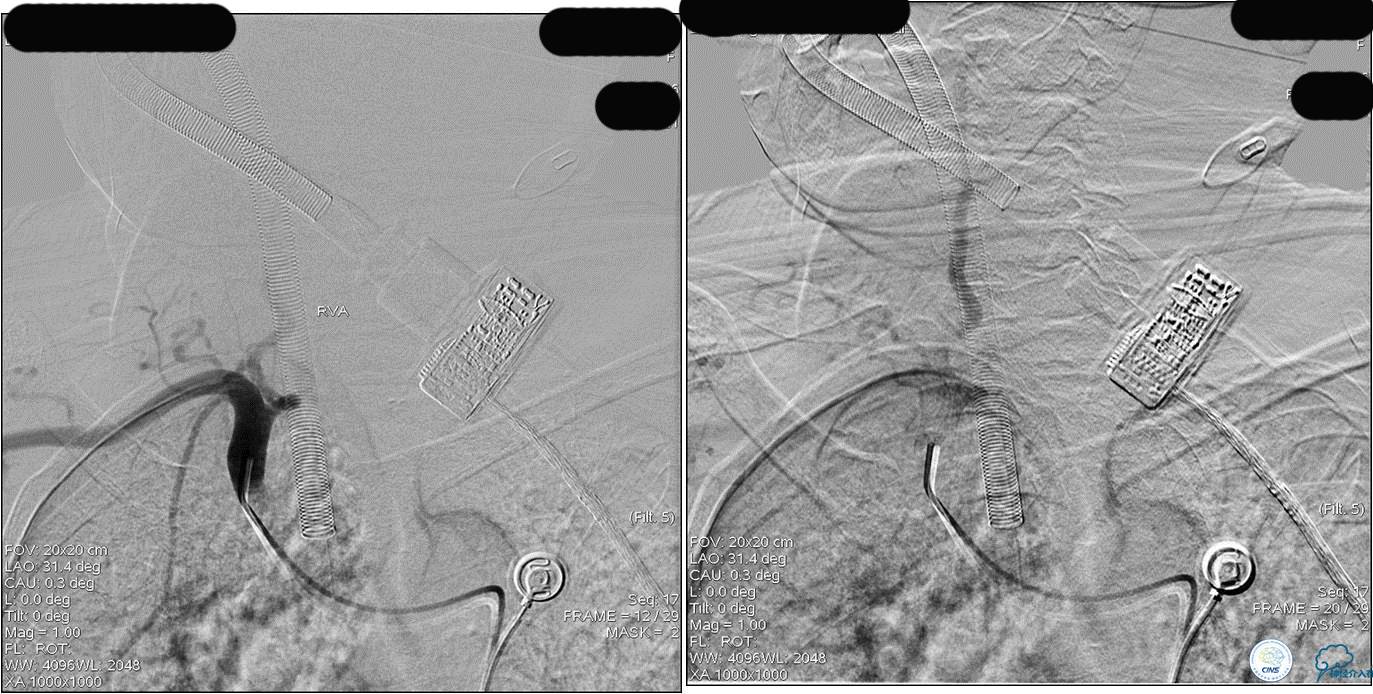

》DSA资料(前2次取栓,未取出,soli 4-20)